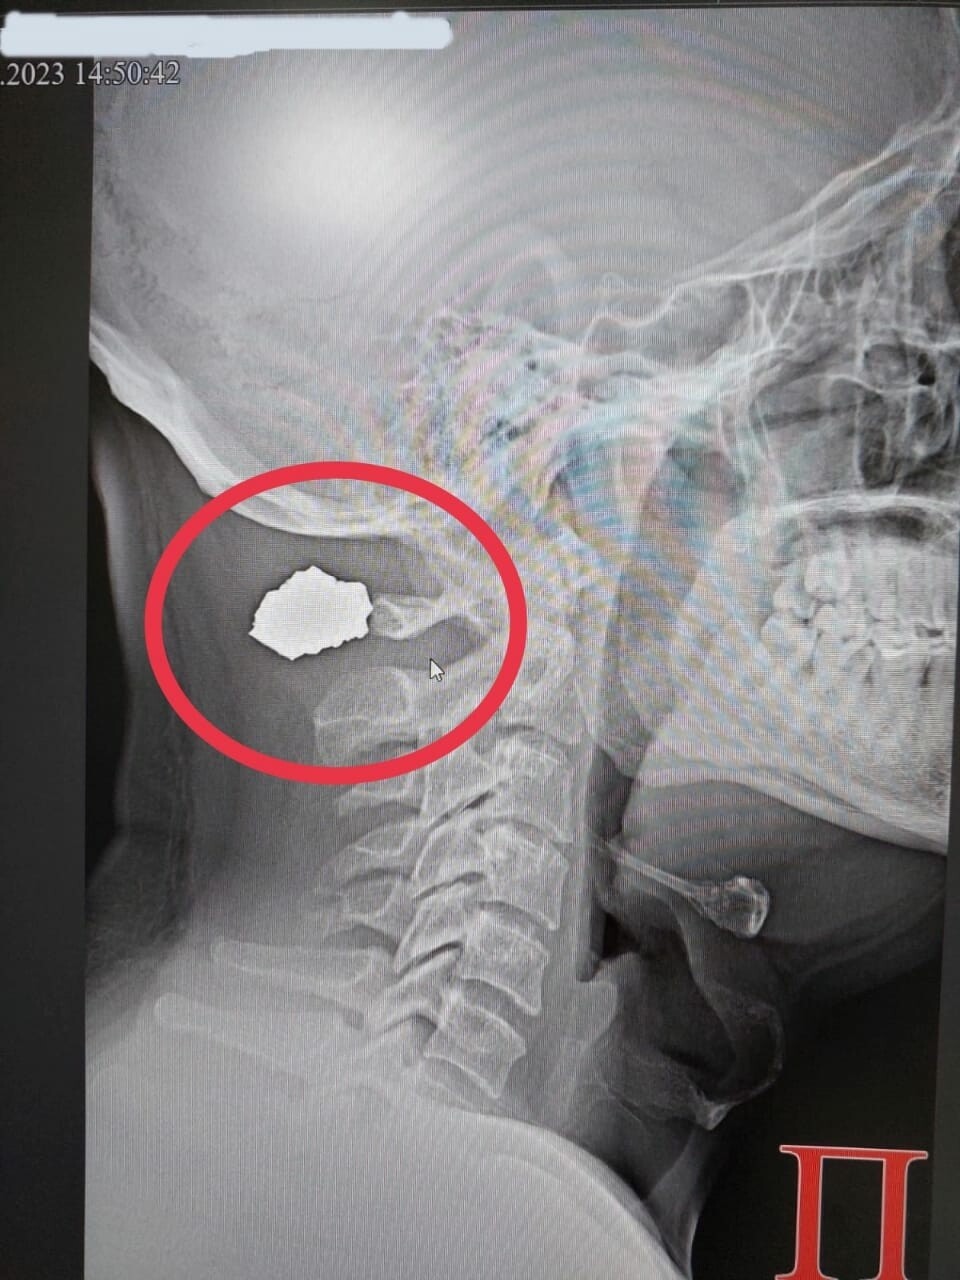

Травмы: что делать при ранении осколком